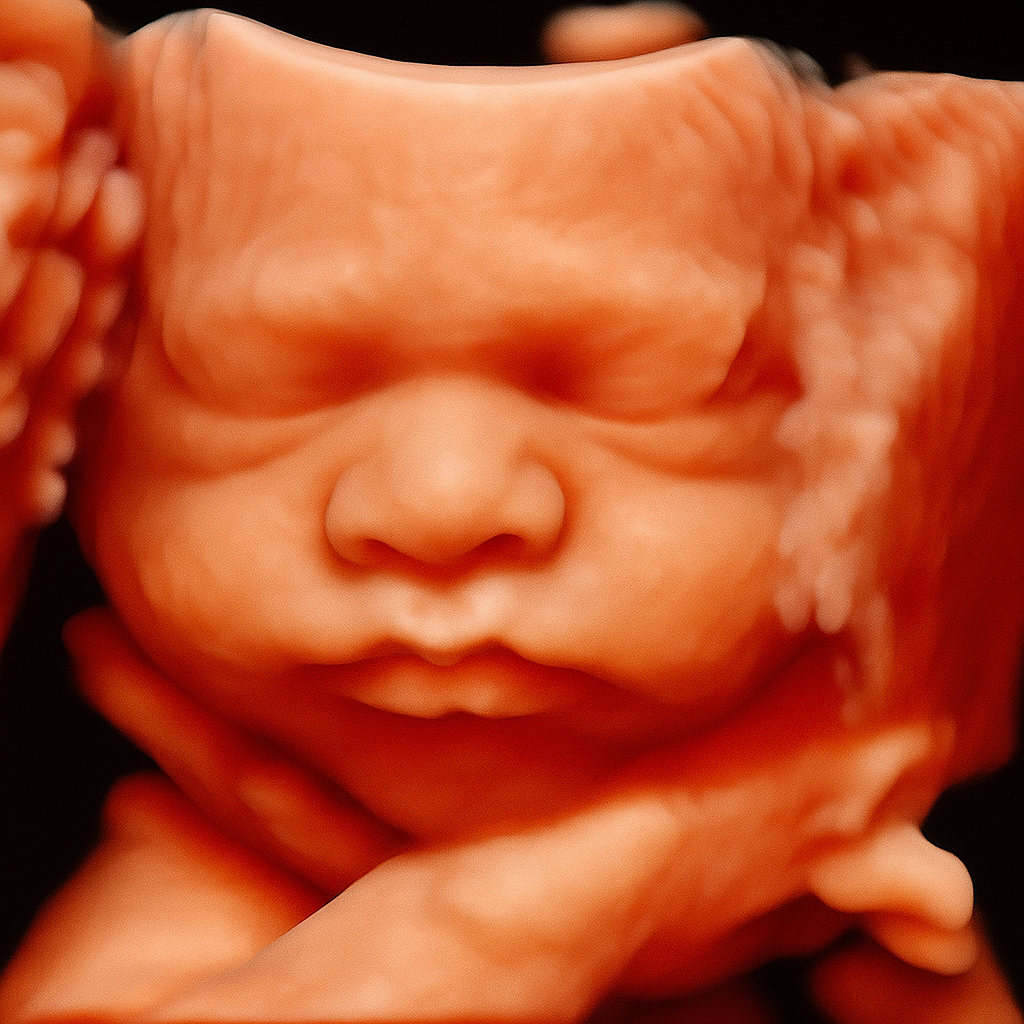

La tecnología 5D nos permite observar los gestos, sonrisas y movimientos de tu bebé con una nitidez excepcional, creando un vínculo emocional profundo desde el embarazo. No es solo una imagen, es un recuerdo para toda la vida.

La ecografía 3D muestra imágenes estáticas, la 5D añade movimiento en tiempo real con mayor nitidez, y la foto HIPERREALISTA ofrece una calidad mas clara de la cara del bebe y con detalles únicos.

La imagen Hiperreal consiste en el tratamiento posterior de la ecografía 5D siendo una simulación que mejora texturas y forma la ecografía, no es una copia fiel y exacta a como será el bebé si no una imagen hiperreal que se asemeja a un bebé recien nacido, al ser una simulación Veo Veo Bebés no se responsabiliza del resultado final y las expectativas de cada cliente, pues al trabajar con inteligencia artificial esta le dará el resultado que considere.